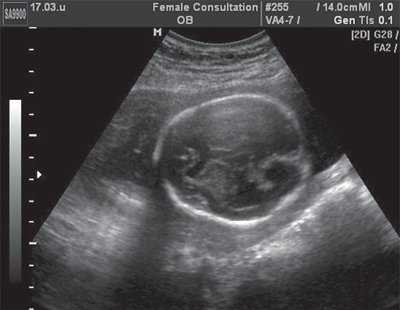

При сравнении изображения в 2D режиме, по которому производились первоначальные измерения, и ультразвукового среза, полученного ретроспективно из сохраненного объема видны ошибки, допущенные при измерениях (рис. 4), и прежде всего отсутствие четкой картины четырехкамерного среза сердца и небольшое увеличение снимка. На этом этапе работы использование новых технологий позволило нам более объективно оценить ранее полученные данные.

а) Нарушены правила оценки: нет четкого изображения четырехкамерного среза сердца.

Случай пренатальной ультразвуковой диагностики сочетания порока Арнольда-Киари с диафрагмальной грыжей, микрогенией и гипотелоризмом

При ультразвуковом исследовании в полости матки определялся один живой плод в головном предлежании, показатели фетометрии соответствовали 22 недель беременности. В результате эхографического обследования головного мозга в горизонтальной плоскости обнаружена вентрикуломегалия, отмечено увеличение ширины задних рогов боковых желудочков и отсутствие изображения большой цистерны. Кроме этого, была выявлена ромбовидная структура в области цистерны четверохолмия.

При горизонтальных сканированиях выявлена характерная, заостренная кзади ("ланцетоподобная"), форма задних отделов тела бокового желудочка. Отмечена также асимметрия расположения сосудистых сплетений боковых желудочков, отсутствие изображения прозрачной перегородки (рис. 1). При фронтальных сканированиях через лобные доли у плода выявлено их атипичное изображение, которое проявилось в полном отсутствии изображения латеральных субарахноидальных пространств. При сагиттальном сканировании обнаружено увеличение расстояния между задней поверхностью валика мозолистого тела и верхней поверхностью червя мозжечка (рис. 2).

Рис. 1. Поперечное сечение головы плода, горизонтальное сканирование. Изображение прозрачной перегородки отсутствует.

Рис. 2. Сагиттальное сканирование головы плода. Выраженное увеличение высоты тела бокового желудочка.